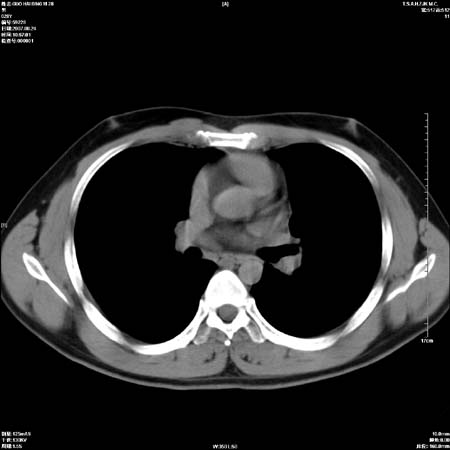

男性,28岁,体检发现左肺病变,患者只有背部隐痛感,哀哉,真不忍心下诊断啊。

左肺门区软组织肿块,左肺上叶支气管开口消失,纵隔内见肿大淋巴结,考虑左中心型肺部,可以做纤支镜取病理确认.

左肺肺门区肿块影,分叶明显,左肺上叶支气管开口受压,纵隔内见肿大淋巴结,考虑左中心型肺癌。